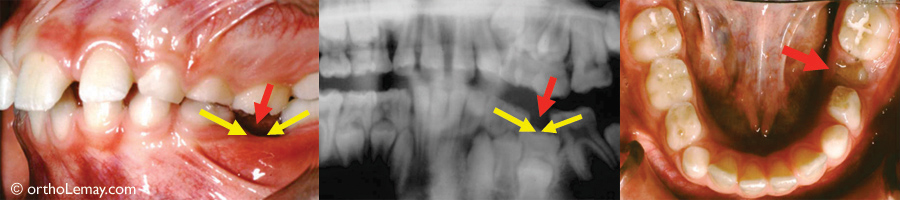

L’ANKYLOSE d’une dent peut apparaître pendant les corrections orthodontiques. Ce patient de 15 ans a une absence congénitale (anodontie) des deuxièmes prémolaires inférieures (X rouge) . La molaire temporaire droite (1 et * bleu) demeure au même niveau que les autres dents pendant le traitement et la croissance verticale de la mandibule tandis que celle de gauche (2) qui devient ankylosée, reste plus basse et ne suit pas les autres dents qui continuent leur éruption. Ceci est visible en comparant le niveau des dents sur une radiographie avant le début du traitement (A) et pendant les corrections. (B) La flèche indique l’importante décalage de niveau vertical entre les dents. À noter que les 2 molaires temporaires n’ont eu aucune attache (boîtier) pendant les corrections.